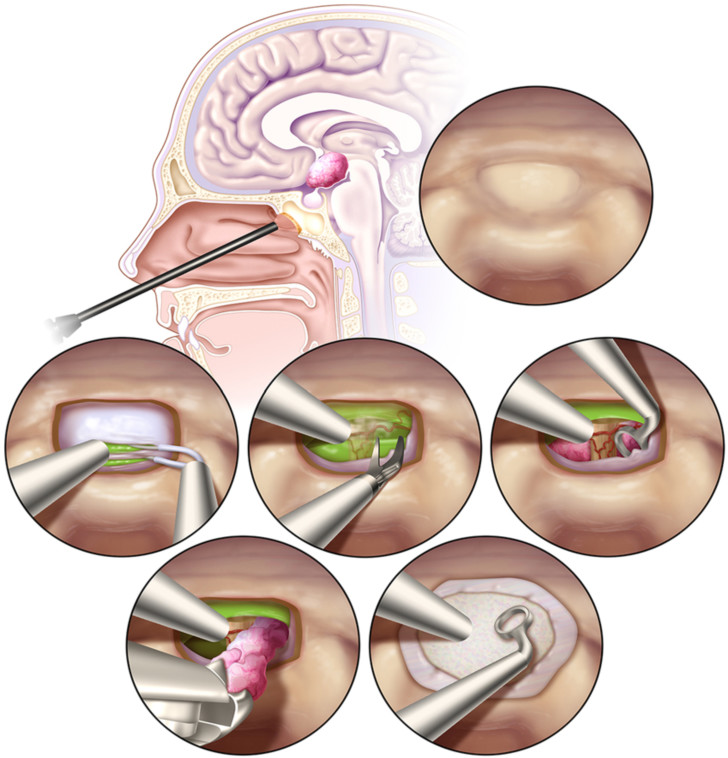

20. 第三脑室内颅咽管瘤的鼻内窥镜经蝶窦切除术:手术结果

Endonasal endoscopic transsphenoidal resection of intrinsic third ventricular craniopharyngioma: surgical results

Author: Jonathan A. Forbes, Edgar G. Ordóñez-Rubiano, Hilarie C. Tomasiewicz, Matei A. Banu, Iyan Younus, Georgiana A. Dobri, C. Douglas Phillips, Ashutosh Kacker, Babacar Cisse, Vijay K. Anand and Theodore H. Schwartz

DOI: https://doi.org/10.3171/2018.5.JNS18198

第三脑室内颅咽管瘤(IVCs)已被业内认为是所有颅咽管瘤(CPAs)中“构成最大的手术挑战”的一类。各种开放性显微外科手术方法已被用于切除这类肿瘤。尽管近年来越来越多的专家会使用鼻内镜入路(EEA)的方法,但许多研究人员仍然建议不使用EEA的方法来切除IVCs。本文作者报道了迄今为止最大数量的利用EEA去切除IVCs。

研究人员回顾了过去14年前瞻性地的手术病例,在纽约长老会医院与威尔康奈尔医学院中通过EEA切除IVCs的数据。术前检查MRI的结果被两名独立神经外科医生和一名神经放射学家用于鉴定IVCs。而患者的术前和术后的内分泌、眼科或放射学以及其他相关疾病情况,则通过回顾性的图表和容量放射学分析来确定。

在2006年1月至2017年8月期间,共10名患者(4名男性,6名女性),年龄从26岁到67岁不等,接受了利用EEA方式的IVCs切除术。术前内分泌障碍患者占70%,而视力下降患者占60%。在该10例患者中,有9例(90%)实现了全切除,其余患者实现了近全切(98%),30%的患者病理为鳞状乳头型。有采用封口“密封垫”技术,利用鼻中隔皮瓣覆盖并进行腰大池引流(9例)或脑室引流(1例)。术后患者,分别有90%和70%的患者存在完全的垂体前叶和垂体后叶功能不全。此外,有4例患者的术前视力正常,3例术后视力稳定。另外,其中一位病人在术后发现了不协调的眼斜视。在6例视力低下的患者中,2例术后视力稳定。其余4例患者肿瘤切除后视力均有明显改善,1例患者视力完全恢复正常。除了上述的一病例(10%)外,没有术后神经功能下降的病例。而1例病态肥胖患者术后发生脑脊液漏的情况,需要再次手术进行修补。在平均随访46.8个月(4-131月)后,2例患者(20%)出现肿瘤复发,1例接受放疗,1例接受化疗。而这两名患者都是第三脑室内颅咽管瘤全切者。

本研究报告中描述的10例患者是迄今为止使用EEA进行切除治疗的最多的IVC患者。EEA切除第三脑室内颅咽管瘤属于一种安全有效的手术方式,应被认为是治疗这类具有挑战性的肿瘤的一种较优的手术方式。

图:IVCs切除的手术步骤示意图。

【张继】